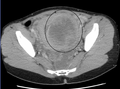

A very large (9 cm) fibroid of the uterus which is causingpelvic congestion syndrome as seen on CT |

While a bimanual examination typically can identify the presence of larger fibroids, gynecologic ultrasonography (ultrasound) has evolved as the standard tool to evaluate the uterus for fibroids. Sonography will depict the fibroids as focal masses with a heterogeneous texture, which usually cause shadowing of the ultrasound beam. The location can be determined and dimensions of the lesion measured. Also magnetic resonance imaging (MRI) can be used to define the depiction of the size and location of the fibroids within the uterus.